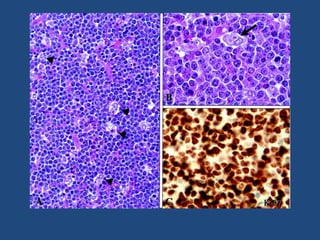

• Les cellules du LB ont un rapport nucléo cytoplasmique

élevé.

• Le noyau est rond ou ovale avec un aspect de chromatine

ouvert.

• Ce noyau contient plusieurs nucléoles (2 à 5).

• L’index mitotique est élevé.

• Le cytoplasme est basophile avec de nombreux vacuoles;

• Des macrophages contenant des débris cellulaires sont

interposés entre ces cellules monomorphes réalisant l’aspect

de « ciel étoilé ».